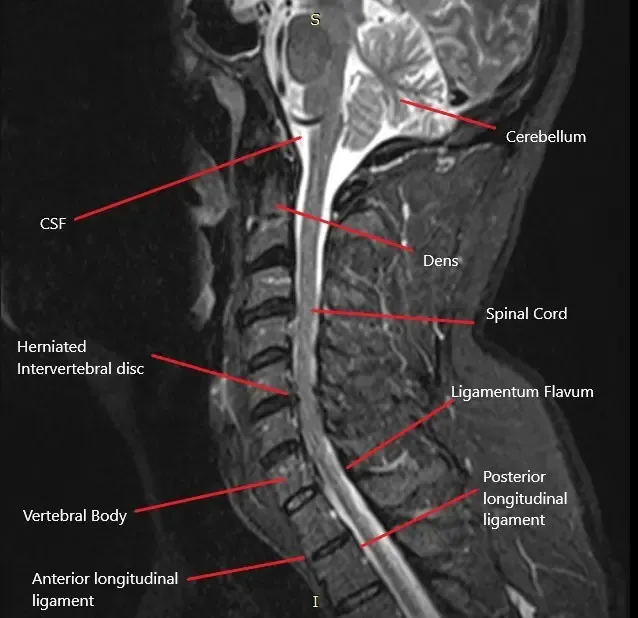

How the Body Part Normally Works? (Relevant Anatomy)

The cervical spine consists of seven vertebrae (C1-C7) in the neck region. Between each vertebra is an intervertebral disc that cushions and allows movement between the bones. The spinal cord passes through the central spinal canal, and nerves branch out from the spinal cord through the foramina (openings) in each vertebra. These nerves control sensation and movement in the shoulders, arms, hands, and other areas of the upper body. When a disc herniates, it can compress one or more of these nerves, leading to cervical radiculopathy.

- MRI: The gold standard imaging technique for identifying herniated discs, nerve compression, and other spinal abnormalities.